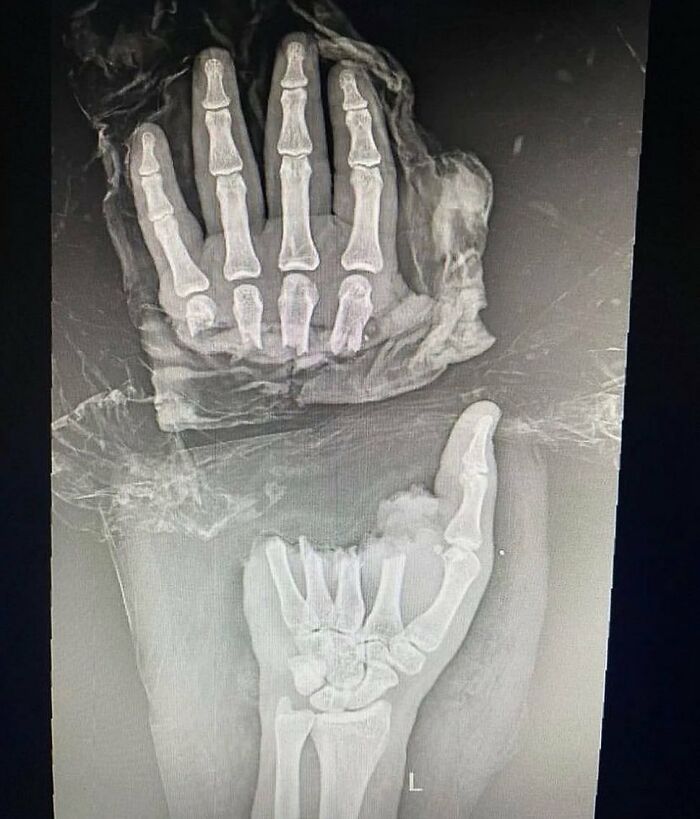

#11 Guy Comes In With Amputation Of The Distal Half Of The Hand Resulting In Complete Separation Of Four Fingers At The Level Of Metacarpals

What do you think caused this injury?

Let your mind go wild on this one.

A. Machete attack

B. Chainsaw

C. Motorcycle crash

D. Manual meat slicer

E. Bear attack

F. Hydraulic press cutting machine

Edit: Answer – B!

Patient presented with traumatic amputation of the distal half of the hand following a work-related chainsaw accident. Full detachment of all four fingers at the metacarpal level.

Obviously, urgent medical evaluation and surgical intervention is needed, but first, let’s just do an x-ray to see if it’s broken, just to make sure.